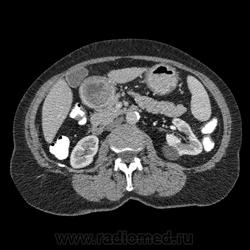

Впечатление, что дуля эта вне головки п.ж., интрамурально в луковице, что ли... тогда возможно GIST, но надо дайком. Утолщение подслизистой в антральном отделе желудка, не удается проследить переход от желудка к 12-перстной((. Внутрипросветно/внутристеночно - не разобрать. 1 фаза?

Клинику! Есть ли признаки высокой тонкокишечной непроходимости, что при ФЭГДС в 12-перстной - туда удалось пройти или нет? ААА! Одни вопросы))))

В-общем, варианты такие без дайкомов: пролапс слизистой в 12перстную, безоар, внутрипросветный дивертикул, гастроинтерстинальная опухоль. И большие сомнения, что это в головке п.ж. - оно отделено от неё тонким слоем жировой клетчатки

Фаз было 3. Видео не выставлял прошлый раз пришел ответ из сайта что видео не работает на сайте Идет накопление контраста в нативе в центре +2+4 по периферии +32+34 .в артериальную +20 и +65 +70 соответственно.

Что оно копит - бог с ним... если это пролапс слизистой, то суммация стенок. Безоар бы не копил. Напрягает отек слизистой в антрале... Это должно быть скорее внутри просвета кишки, т.к. оттесняет газ в 12-перстной на периферию. Без дайкомов больше ничем не могу, извините. Подождём мнения коллег.

Как мне видится - пролапс слизистой желудка в 12-перстную. А мнения коллег что-то нетути...

А что растет из левой почки? Может оно же и желудок сдавливает?

Это расширение всей 12- перстной кишки (стаз).